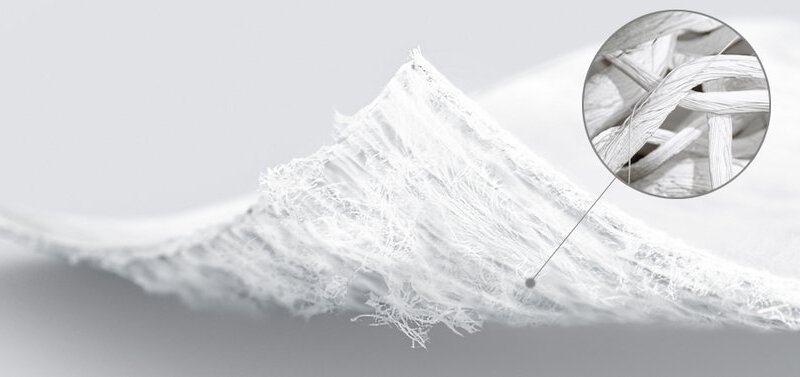

Der zweischichtige Aufbau der Membran unterstütze die Heilung und Regeneration von geschädigtem Knorpelgewebe optimal. Die einzigartige Struktur mit einer glatten, kompakten Oberseite und einer rauen, porösen Unterseite bietet ideale Bedingungen für Knorpelregeneration, heisst es von Geistlich Pharma zu dem Produkt.